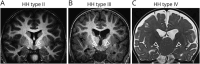

Methods: We recruited 9 HH cases including 8 nonsyndromic cases of which 4 were type IV HH. Genomic DNA was extracted from peripheral blood and surgical brain tissues, and somatic variants were investigated using high-depth whole-exome sequencing.